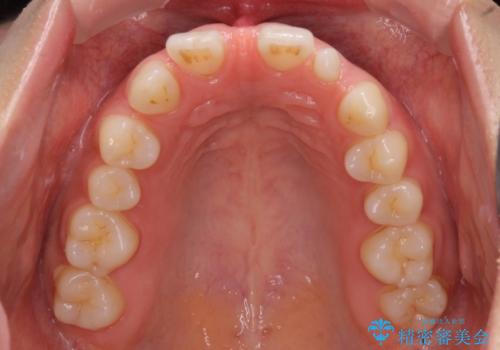

- 前歯の隙間を気にして来院された患者様です。

診察の結果、前歯が1本欠損しており、さらに矮小歯(通常よりも小さい歯)が1本存在していました。

欠損による前歯のスペースが大きかったため、事前にワイヤー矯正で前歯の位置を大きく動かし、その後は上下をインビザラインで整えることとしました。

矯正治療後には欠損部はオールセラミックブリッジに、矮小歯はオールセラミッククラウンにて補綴することとしました。

前歯のスペースは、堅い線維の通った歯肉があり、幅も大きかったことから、歯肉切除を行った上でワイヤー矯正により移動を行いました。また、上唇小帯も歯間部付近まで付着していたため、合わせて切除しました。

ワイヤー矯正により、インビザラインよりも早く、歯軸の向きもコントロールしながら移動させることができました。